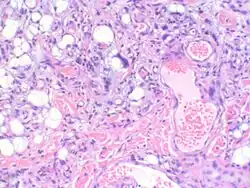

- Myxofibrosarcoma-pathology